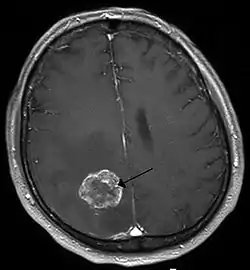

- Brain tumor